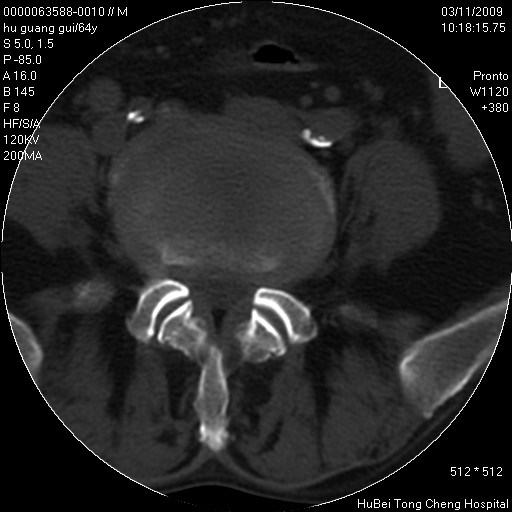

患者 男,64岁。腰痛十余天。(临床未提供其他病史)

临床诊断:腰痛原因待查(腰椎间盘突出症?)。

腰椎间盘ct轴位平扫(层厚5mm,层距4mm),图像如下:

腰椎退行性变,腰4—5椎间盘膨出。

右侧骶骨侧块骨侵蚀,骶髂关节骨性关节面破坏,并见软组织肿块,考虑骨转移瘤可能,进一步检查。

1.腰椎退行性变,腰4—5椎间盘膨出。

2.右侧骶骨侧块骨侵蚀,骶髂关节骨性关节面破坏,并见软组织肿块,考虑:脊索瘤,骨转移瘤可能,进一步检查。

1)腰椎退行性变,l4—5椎间盘膨出。2)骶骨右侧块骨转移瘤可能,3)水平骶椎。建议作一步检查。